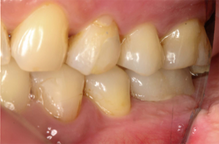

Mr NK, a 52-year-old male, presented with concerns of gradually shortening teeth and sensitivity to cold drinks. He also reported feeling self-conscious about his smile in photos. He is medically fit and has been using a night guard for his sleep-related grinding habit for the past year. Clinical examination revealed moderately worn dentition from erosion and attrition, along with mild crowding of the lower anterior incisors.

Intra-Oral Pictures (Before)

- Erosion severity: ACE Class Class III

- Reduced occlusal vertical dimension

- Mild crowding of lower anterior teeth